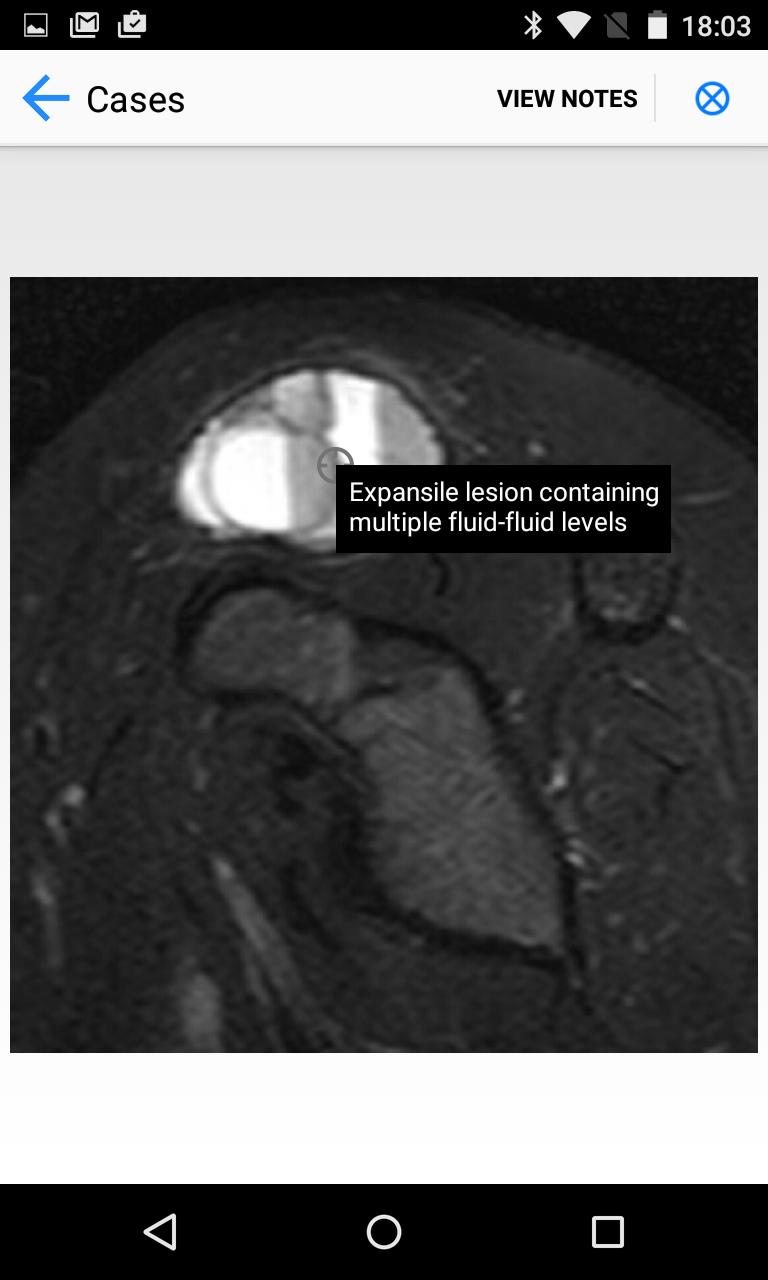

BoSTT bringt dem Benutzer eine echte Erfahrung mit häufigen und seltenen, typischen und ungewöhnlicheren Fällen von Knochen- und Weichgewebe -Tumoren. Jeder Fall hat eine klinische Anamnese, hochauflösende Radiologie- und Pathologie -Bilder, Diagnose, Behandlungs- und Lernpunkte.